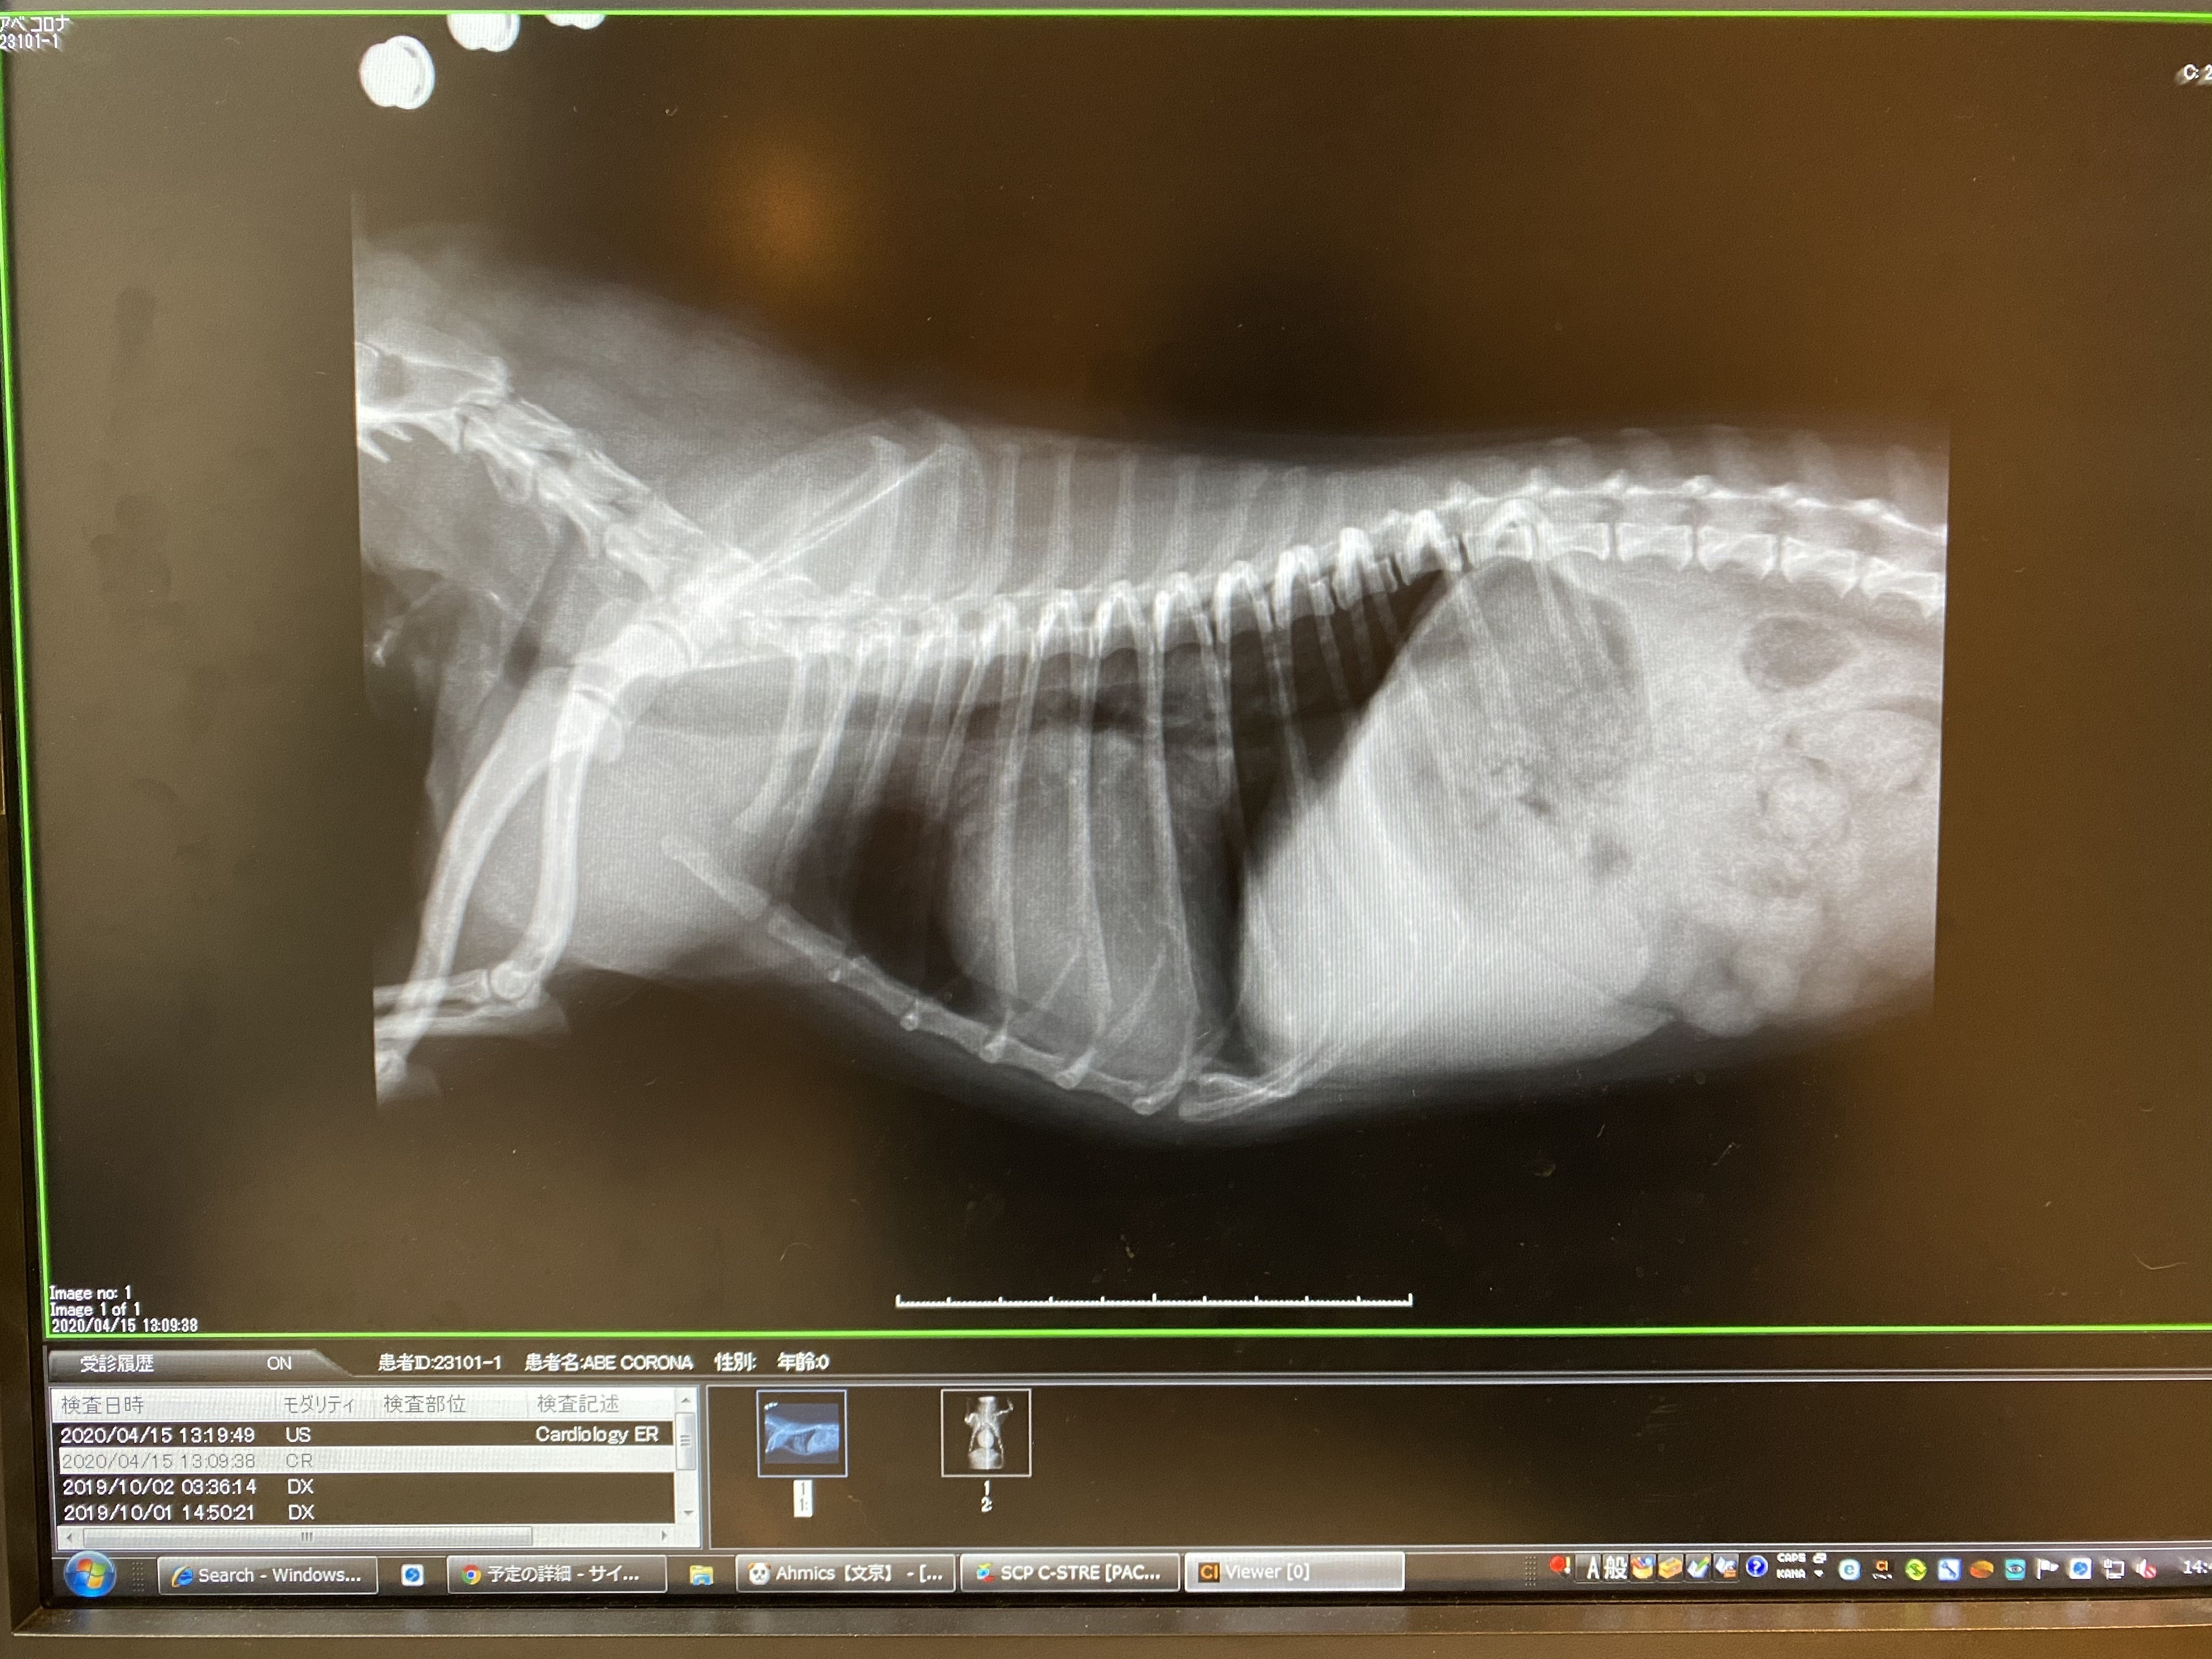

前回の心臓と気道

以前は心臓がパンパン過ぎて気管を押し上げ気道が狭くなっていたのが…

心臓で圧迫されていた気管が今は下がっているのがわかります今回のレントゲンを見てわかる通り、押し上げられていた気管が下がり、気道が確保されていました!